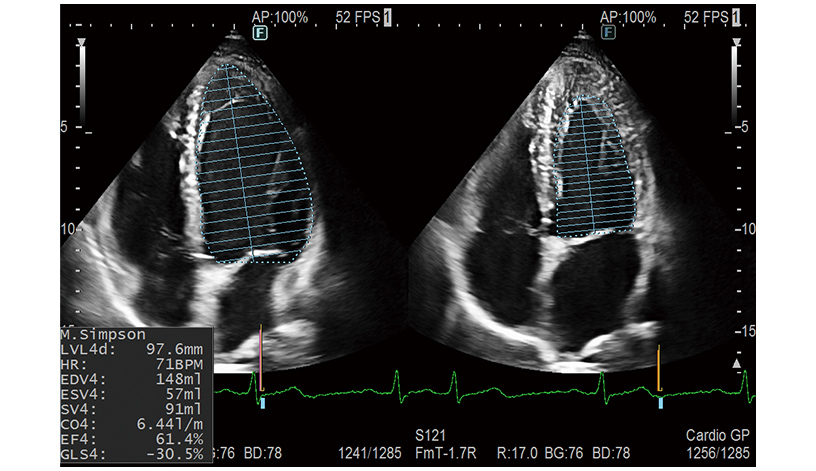

Simpson measurement, which utilizes AI technology*1, automatically recognizes LV, LA and RA intima and measures the volume. Additionally, a wide range of functions are supported to improve the workflow of cardiovascular measurement, such as Doppler Cursor Assist.